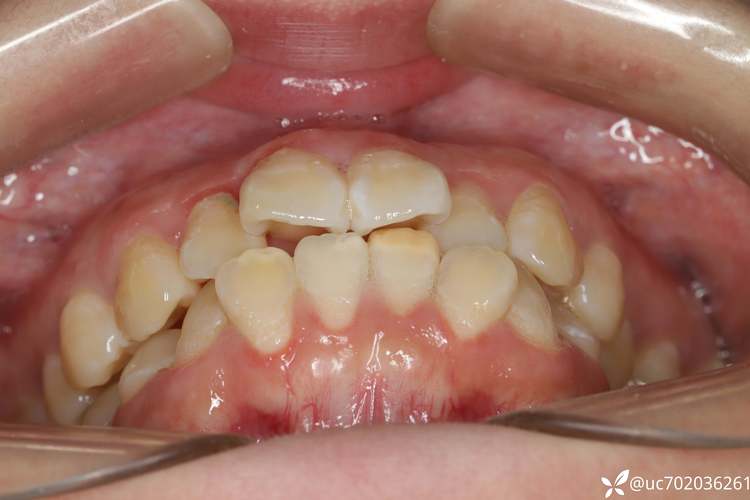

拔牙的核心目的是“调整牙量与骨量的匹配度”,正常情况下,牙齿需要占据颌骨内一定的空间(牙弓长度),当牙齿过多、颌骨空间不足,或牙齿排列异常(如拥挤、前突)时,就需要通过拔牙为其他牙齿的移动创造空间,就像拥挤的房间需要搬走部分家具才能重新布局,拔牙相当于“搬走多余的牙齿”,让剩余牙齿排列整齐、咬合协调。

拔牙需根据牙齿拥挤度、咬合关系、面部美学等综合判断,以下常见情况可能需要拔牙:

| 严重牙齿拥挤 | 牙齿重叠、扭转,拥挤度超过5mm(用牙弓长度与牙齿总宽度差值计算) | 40%-60% |

| 牙齿前突(龅牙) | 上下牙弓前突,嘴唇闭合困难,侧脸轮廓不协调 | 20%-30% |

| 咬合异常 | 深覆合(上牙完全覆盖下牙)、深覆盖(上牙前突超过下牙唇面)、反颌(“地包天”) | 15%-25% |